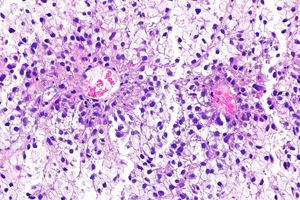

세포나 과립이 방사상으로 배열된 구조는 로제트 또는 로제트양이라고 하며, '''균좌'''라고도 불린다. 신경교종 세포나 말라리아원충의 분열기에서 관찰된다.[8] 파리의 배아 체축 신장, 척추동물의 신경관 형성, 신장 요세관・척삭의 신장 시 등에 보이며, 상피조직에서 수렴 신장의 진행에 기여하는 중간 구조체가 된다.[8]

빗살해파리에서의 '''로제트'''는 '''섬모환'''(せんもうかん|섬모환일본어, ciliated funnel)이라고도 불리며, 위수관계의 벽에 8개씩의 세포가 도넛 모양으로 이중의 고리를 만들어서 겹쳐져 있는 구조이다[8]。 위수관계의 내강 측 세포에는 짧은 직모가, 간충겔 측 세포에는 긴 섬모가 있다[8]。 이러한 섬모 운동에 의해 위수관계의 물과 영양분이 간충겔 내로 보내진다[8]。원신관의 불꽃세포와 비슷하며, 배설기관이라고도 한다[8]。세포나 과립이 방사상으로 배열된 구조를 '''로제트''' 또는 '''로제트양'''이라고 한다[8].'''균좌'''라고도 불리며, 신경교종 세포나 말라리아원충의 분열기에 보인다[8]。